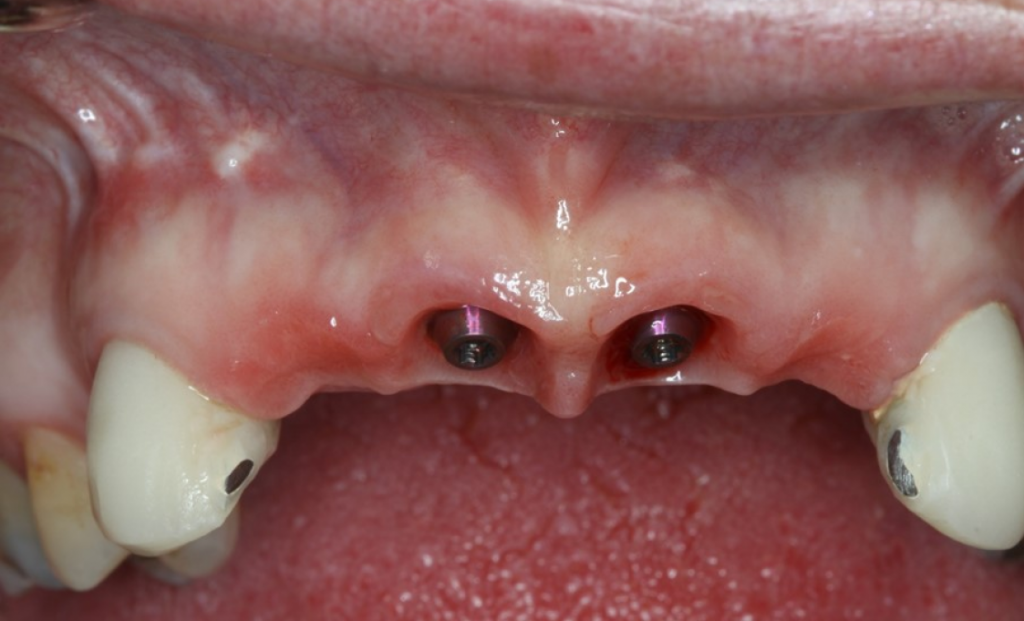

Клинический пример: пациент сломал левый центральный резец и решил удалить все четыре передних зуба и заменить их коронками с опорой на имплантаты.

Рис. 15 Работа с уровня имплантата с имплантатами с внутренним соединением осложняется отсутствием параллельности соседних зубов

Множественные имплантаты редко располагаются параллельно, что затрудняет использование супраструктуры для имплантатов, установленных на уровне кости. Обычно абатменты размещаются ниже уровня мягких тканей, к ним трудно получить доступ. Существуют винтовые и мостовидные абатменты, которые можно использовать на уровне имплантата, но их использование может способствовать смещению костного гребня и потере кости.